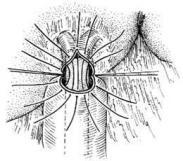

颈部勒伤

628健康网为您分享有关颈部勒伤的症状,颈部勒伤的治疗方法,颈部勒伤的预防知识,颈部勒伤的症状图片,颈部勒伤吃什么药,颈...

颈部开放性损伤

628健康网为您分享有关颈部开放性损伤的症状,颈部开放性损伤的治疗方法,颈部开放性损伤的预防知识,颈部开放性损伤的症状...

颈部脊髓损伤

628健康网为您分享有关颈部脊髓损伤的症状,颈部脊髓损伤的治疗方法,颈部脊髓损伤的预防知识,颈部脊髓损伤的症状图片,颈...